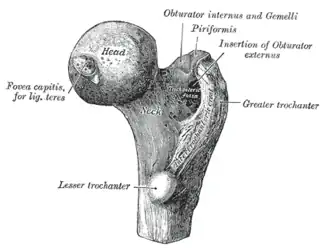

Upper extremity of right femur viewed from behind and above. | |